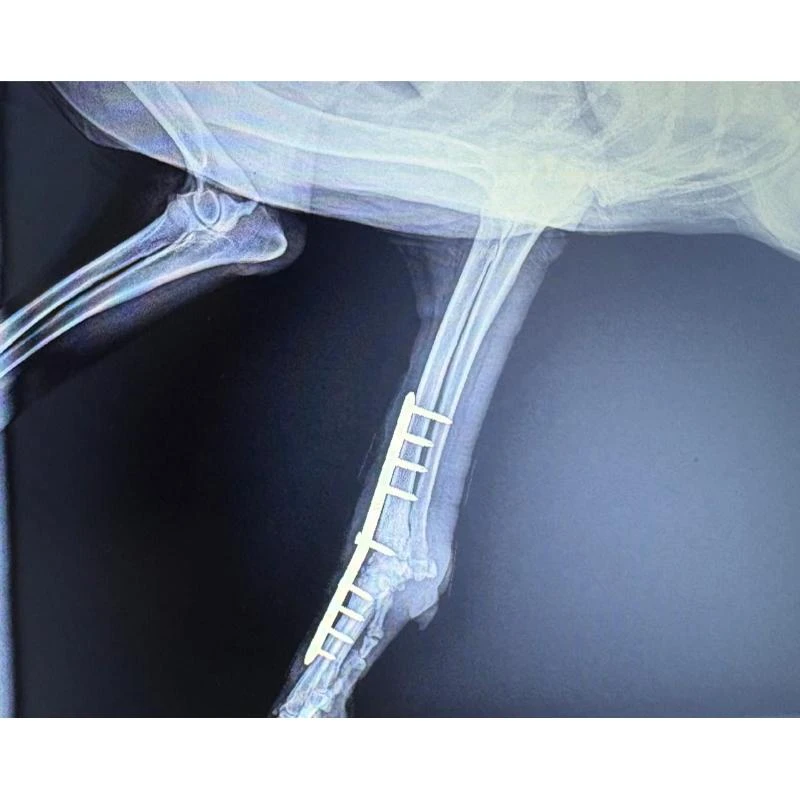

A ortopedia para cães desempenha um papel fundamental no diagnóstico e tratamento de alterações ósseas, articulares e musculares em cães e gatos.

Com recursos avançados de exames de imagem e técnicas modernas, os ortopedistas especializados conseguem proporcionar um atendimento de qualidade, promovendo o alívio da dor, melhora da mobilidade e recuperação funcional eficaz.

O ortopedista cachorro na Grande Florianópolis oferece um atendimento especializado para cães com alterações ósseas e articulares, incluindo fraturas, luxações e doenças degenerativas.

Utilizando exames de imagem detalhados e técnicas terapêuticas modernas, o profissional promove diagnósticos precisos e tratamentos personalizados, visando sempre o bem-estar do animal.